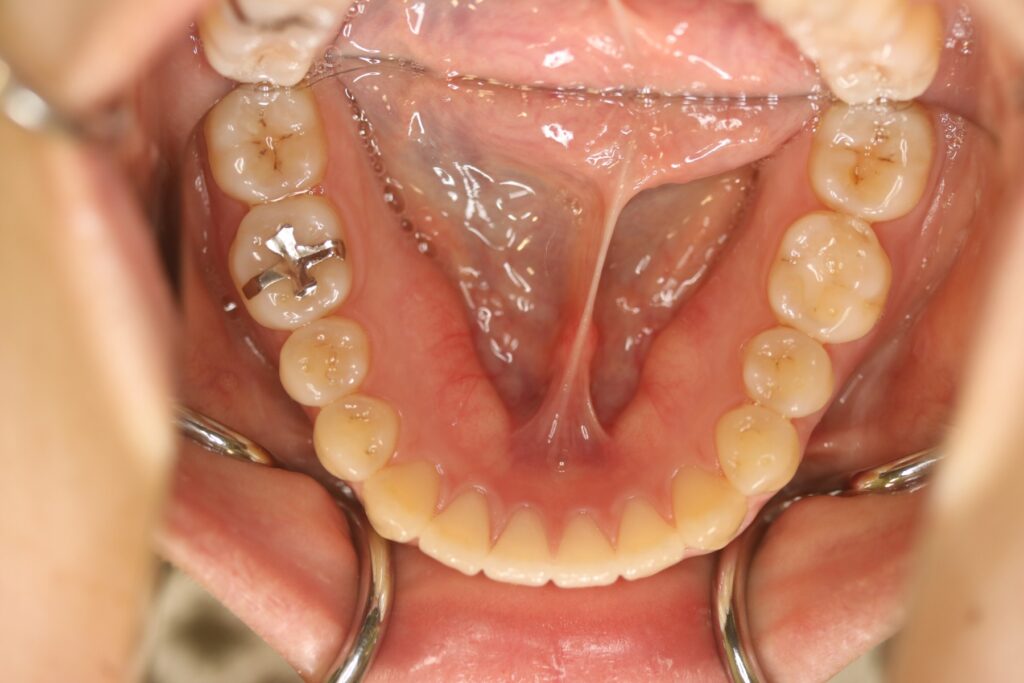

治療実績(症例) アライナー矯正 症例1 上顎前突症例 症例2 上下顎前突症例 症例3 叢生 症例4 開咬 症例5 開咬(外科的矯正治療) アライナー矯正 Post Share Hatena Line RSS feedly Pin it note 1.主訴2.診断名3.初診時年齢4.治療に用いた主な装置とオプション5.抜歯部位6.治療期間・通院回数7.総額と費用内訳総額相談検査・診断料調整料4,000円8.リスク・副作用 治療前 治療中 治療後